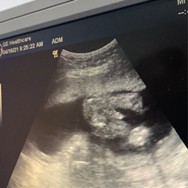

แล้วแบบนี้ล่ะค่ะ5เดือนแล้วญ/ชค่ะ

ดูแบบไหนกันค่ะ หมอบอกว่ายังไม่มีอะไรโด่ออกมา 5เดือนแล้วก็น่าจะรู้แล้วน่ะค่ะ